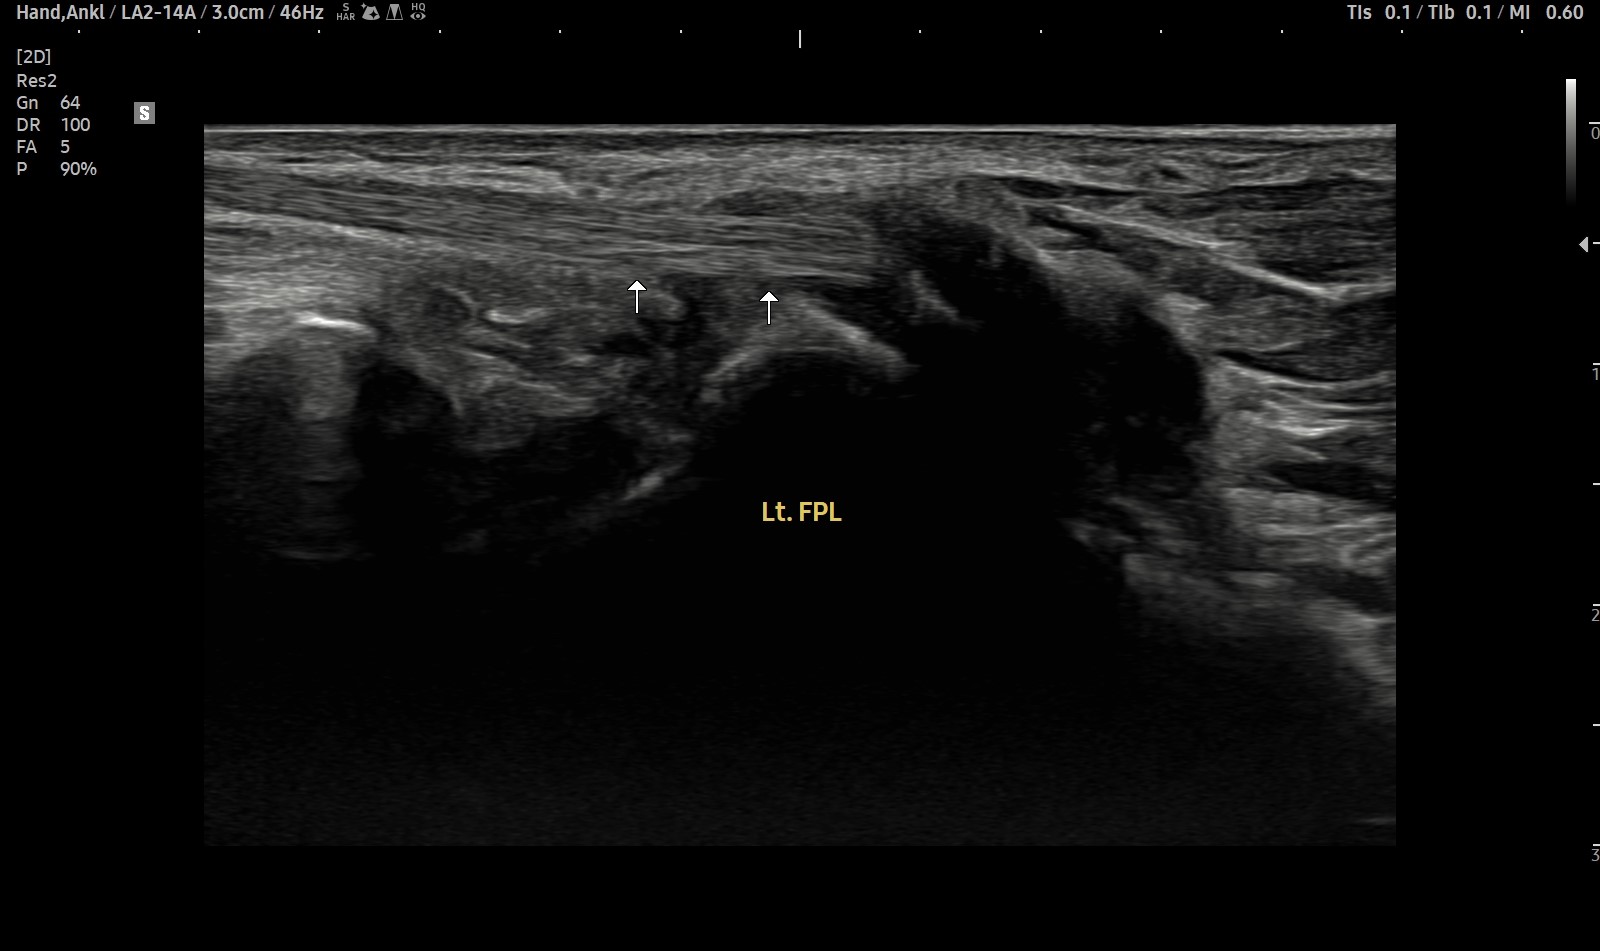

- 치료기간 : 25 . 5 . 7 ~ 25 . 8 .12

- 치료횟수 : 4cycle(20) 회

치료전

치료후